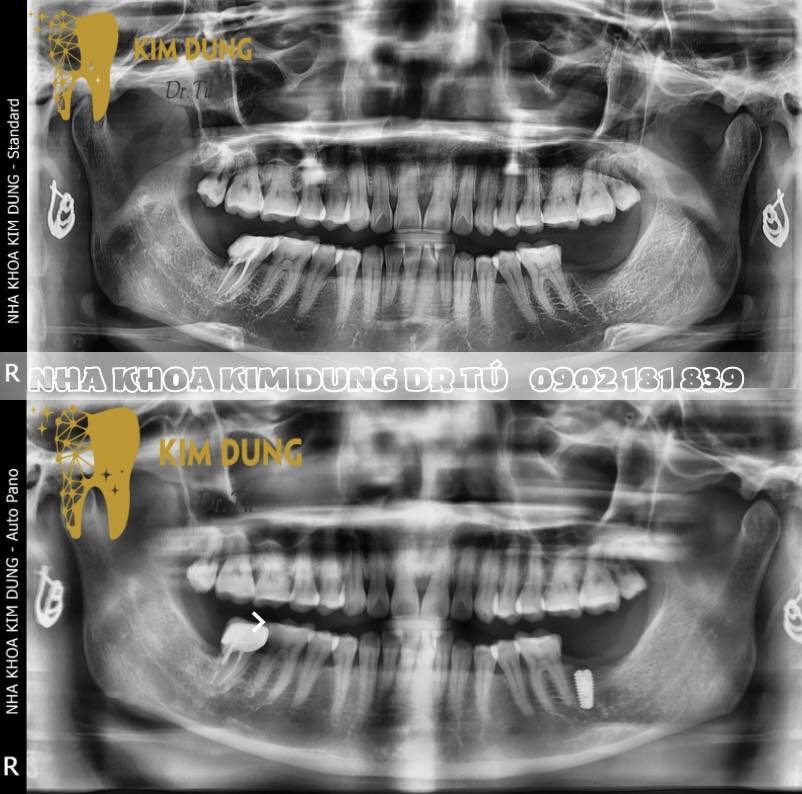

* Quy trình chuẩn đoán trước cấy ghép implant được thực hiện bằng công nghệ tiên tiến, giúp định rõ vị trí và kích thước phù hợp với mỗi bệnh nhân.